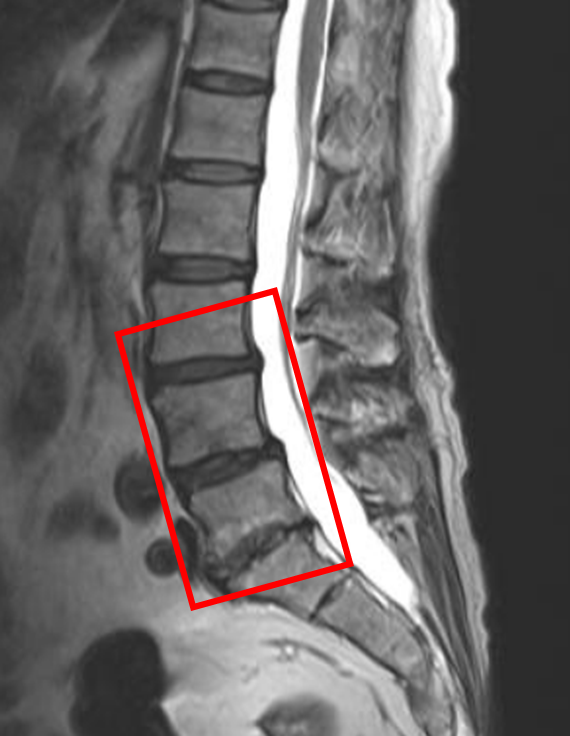

【治療経過のご紹介 No.205】すべり症によって外科手術を提案された患者様

この患者様は赤い枠で示されている箇所(L3/4,4/5,5/s)に椎間板変性症を認めます。